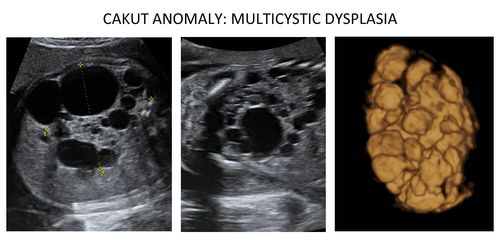

CAKUT comprise a spectrum of structural abnormalities of the kidney and urinary tract that occur in 1:500 foetuses and cause death early after birth in 1:2000 live-born children. The CAKUT spectrum encompasses absence of kidneys (renal agenesis), hypoplasia (reduced number of nephrons) malformed cystic kidneys (multicystic dysplasia figure 1), double renal collecting system, and abnormalities of the tracts, which connect the kidneys with the bladder (ureters). CAKUT constitutes the major cause (70%) of end-stage renal disease in children, which is a devastating disease with a major impact on growth, maturation, and disturbed cognitive development. Patients become dependent on chronic dialysis and/or transplantation and have a poor life expectancy. Therefore knowledge of the causes of CAKUT and the identification of reliable prognostic biomarkers is essential for early and correct diagnosis, prediction of the risk for progressive disease, and the development of personalized therapies to protect the function of the kidney.

- Figure 1: Left two pictures: Ultrasound of the kidney showing the multiple cysts (dark holes). Right picture: 3-D ultrasound allowing to determine kidney volume.